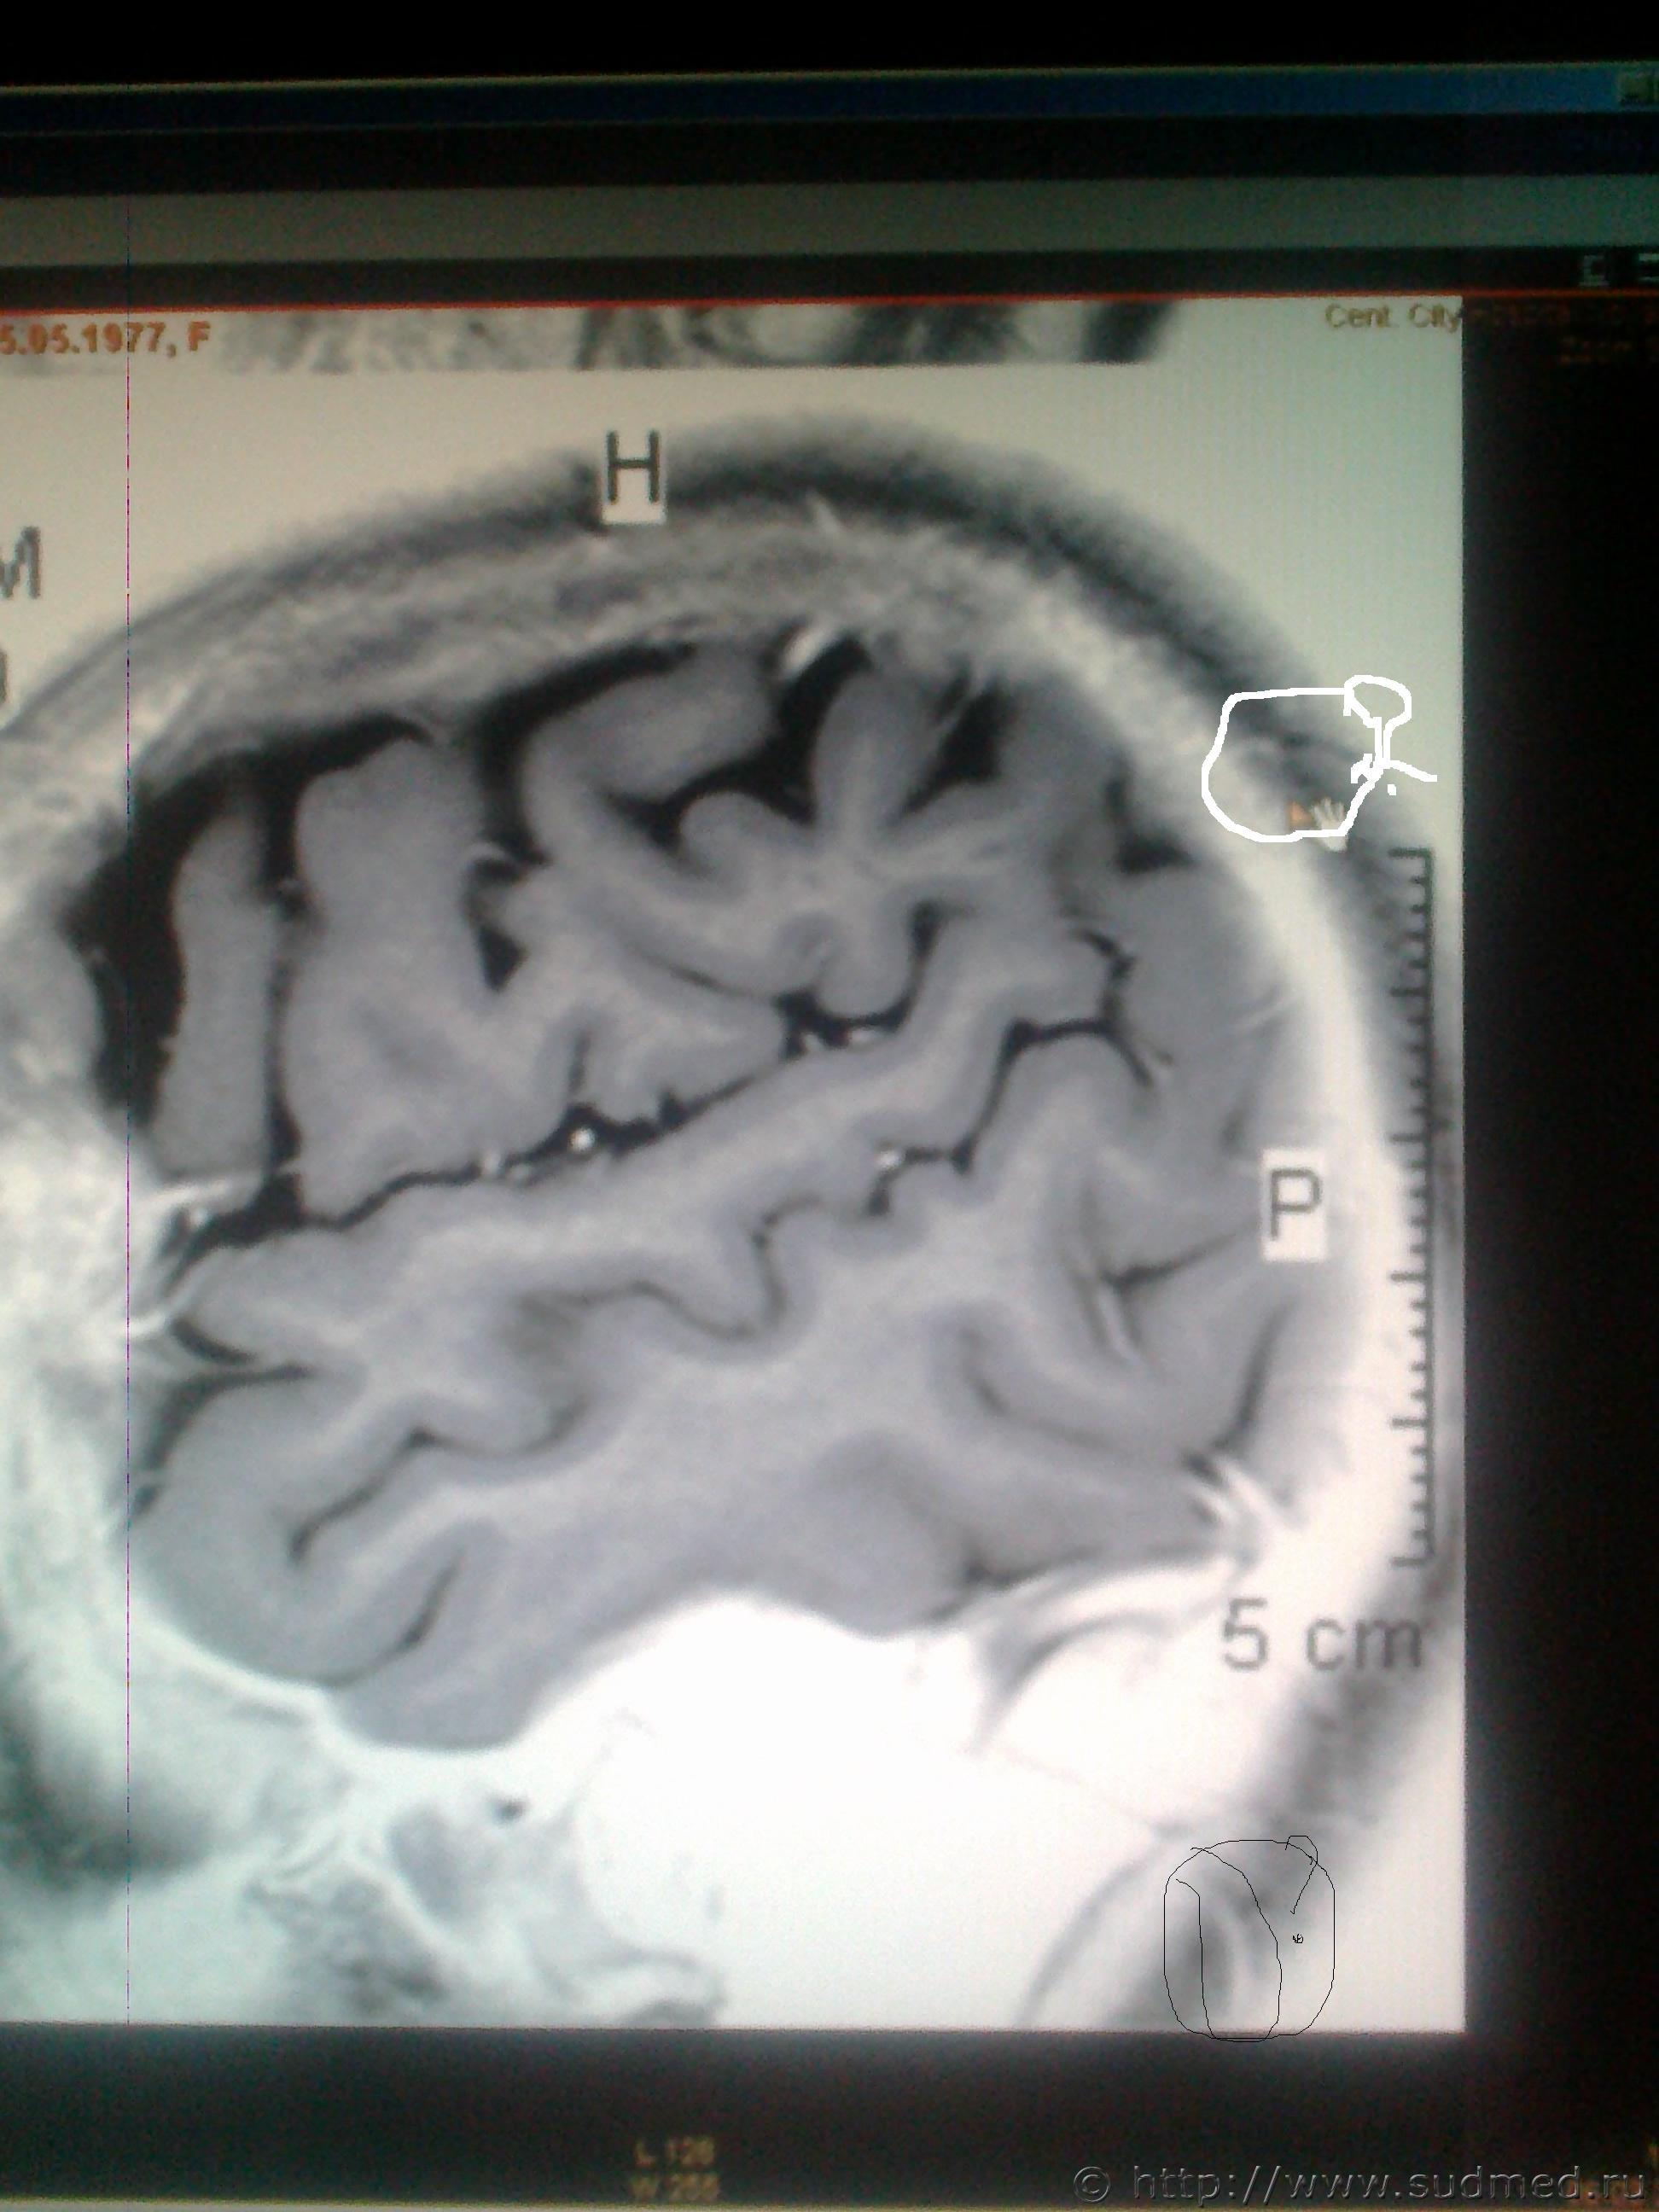

ув. специалисты! Мне оч. хочется узнать ваше мнение, что показано на мрт снимках в мозгу и на костной ткани, интересующие места обведены. Есть ли трещины на костях черепа или это шов и что значит чёрное- белое пятно на снимке мозга?

Светичок! Надо показать сами эти снимки специалисту по МРТ (на пленке и/или на электронном носителе. На эл.носителе даже лучше, т.к. на пленке могут быть распечатаны, к примеру, 30 сканов, а, фактически, их 150 было выполнено и все они могут быть представлены Вам на диске или на флешке). Присланное Вами хуже по качеству, чем снимки, которые есть фактически и, на этом форуме, насколько мне известно, нет врачей имеющих сертификат по специальности"Рентгенология" и дополнительную специальную подготовку по ядерно-магнито-резонансной томографии. Поищите какой-нибудь форум рентгенологов, вероятно, там смогут дать более компетентные комментарии. Насколько я разбираюсь в МРТ (немножко): на снимках №1, 2 и 3 - вероятнее всего, ликворная киста. Возможно, это вариант развития, возможно, след от давно регрессировавшей (прошедшей, рассосавшейся) гематомы. В любом случае, даже если это изменение имеет посттравматическое происхождение, то травма была давно (месяцы или годы назад), на что указывает отсутствие признаков внутричерепной гематомы, перифокального отека вещества головного мозга. Только по этим снимкам ни один специалист не сможет серьезно и аргументированно доказать, что это: 1.именно последствие травмы и ни что другое, 2.точно установить дату этой предполагаемой травмы. (Просьба не путать специалиста с шарлатаном, который, "все что угодно за ваши деньги" - в суде такое "заключение" окажется несостоятельным). На снимках №4 и 5 - шов между затылочной и теменными костями, №6 - каналы диплоэтических вен (вены, проходящие сквозь кости черепа. Они извитые, а перелом, в такой проекции выглядит как прямая линия, перпендикулярно и косо-перпендикулярно пересекающая кость свода черепа). МРТ - неоптимальный метод для оценки состояния костей свода черепа (МРТ - великолепный метод для оценки состояния мягких тканей). Гораздо лучше - обычная рентгенография костей свода черепа. Желательно,сделанная на современном цифровом рентгеновском аппарате. Желательно - полипозиционная (т.е. не только стандартные снимки в прямой и одной из боковых проекций, а, в данном случае - прямая проекция,правая и левая боковые проекции, контактная рентгенограмма затылочной кости и, возможно, снимок с выведением места предполагаемого перелома в краеобразующую зону. Тогда на 100% будет понятно,что это такое. Вероятно, на 100% будет понятно уже на стадии рентгенограмм в прямой и боковых проекциях. Грамотный рентгенолог знает все это лучше, чем я тут написал). Можно, конечно, сделать мультиспиральную компьютерную томографию /МСКТ/ в костном режиме с 3-D реформацией изображения,однако, лучевая нагрузка будет больше, а информативность - сопоставимая. Если в итоге найдется что-то похожее на посттраматические изменения, то нужно будет провести исследование всех рентгенограмм, которые выполнялись непосредственно после конкретной травмы, если когда-то до неё делались рентгенограммы, МРТ, КТ головы - их тоже. Это уже задача судебно-медицинской экспертизы. + будут учитываться данные медицинских карт и прочие документы о лечении после этой травмы, о состоянии здоровья до неё и т.п., т.к. перелом кости/костей свода черепа, внутричерепная гематома протекают с весьма выраженной клинической симптоматикой (от чего-то "легкого" и похожего на "сотрясение головного мозга" до тяжелых невропатологических проблем).